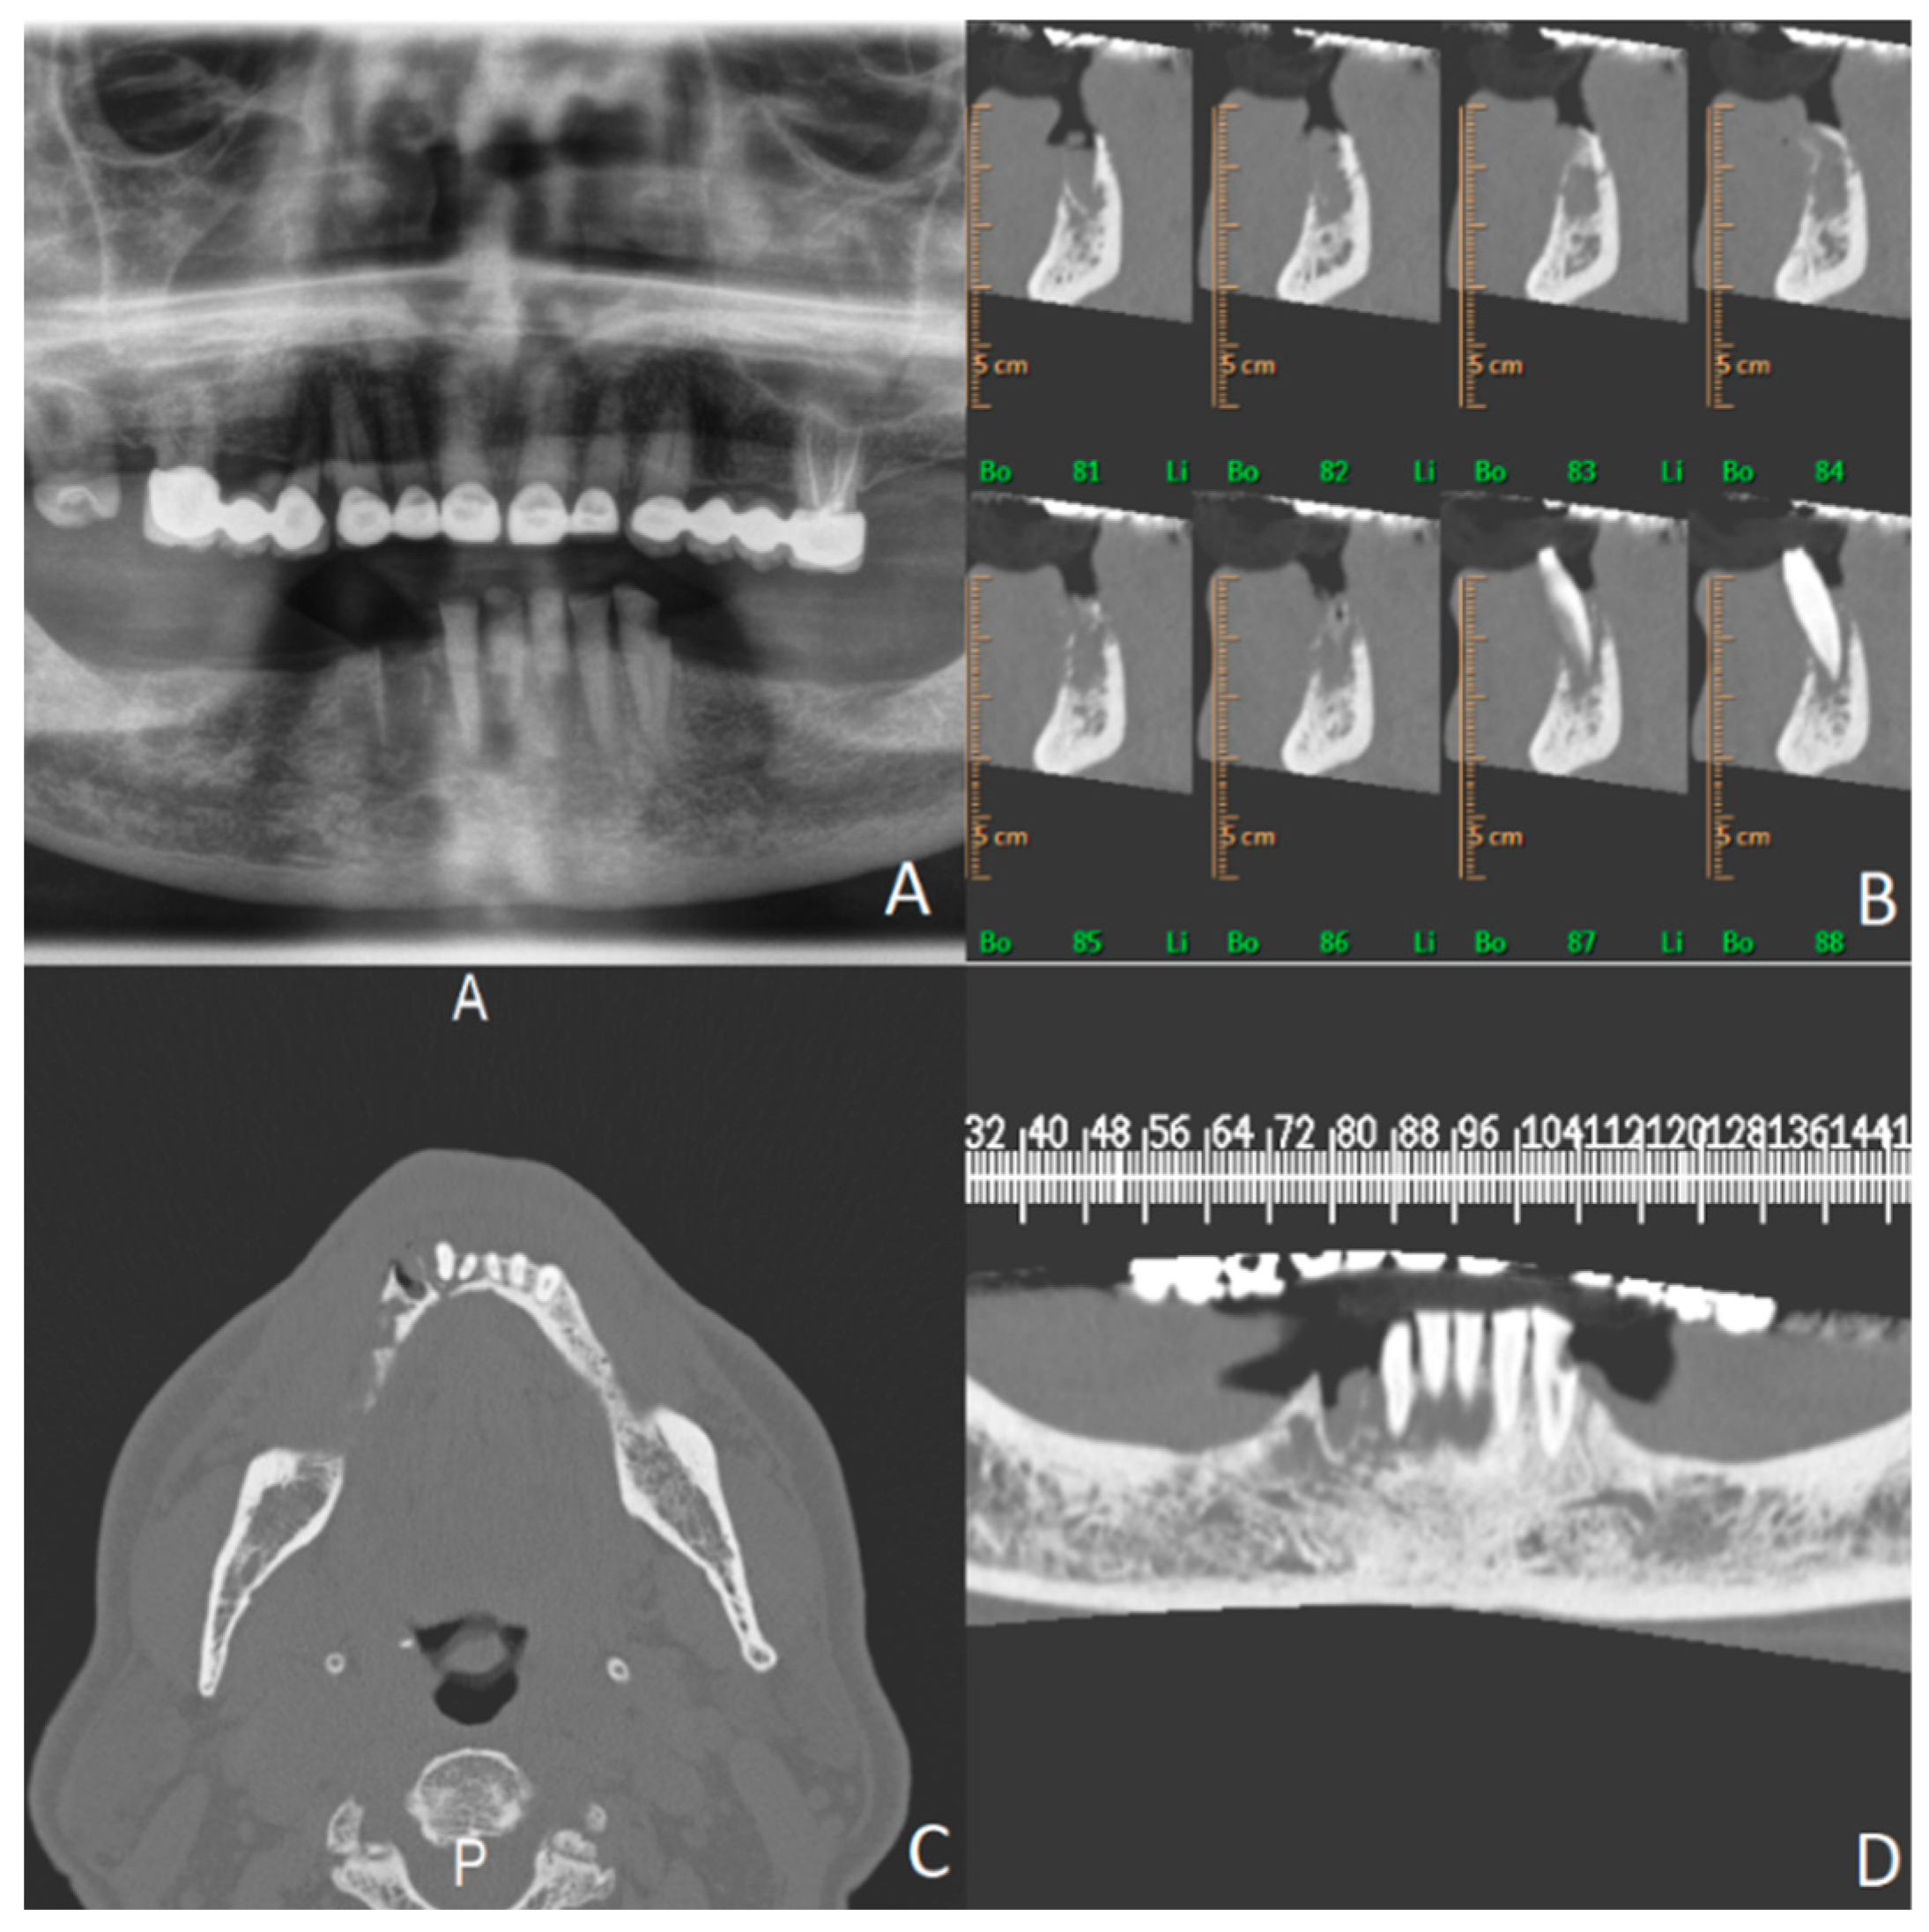

4.8. Case Presentation